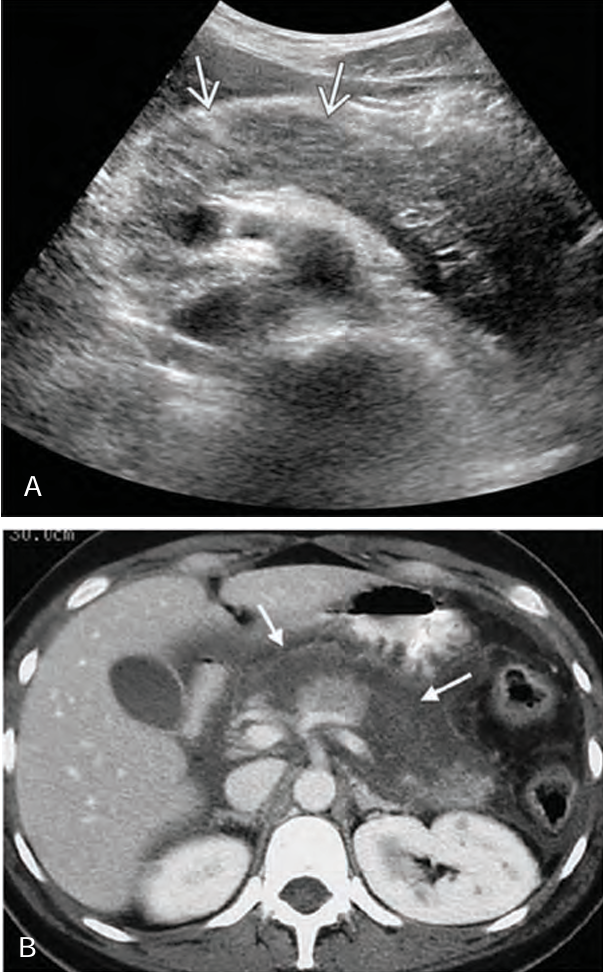

A _______ pancreatitis is an _______ process that spreads along _____ pathways, causing localized areas of diffuse inflammatory _____ of soft tissue that may proceed to necrosis and suppuration

phlegmonous; inflammatory; fascial; edema

______ pancreatitis occurs in ___-___ of patients with _____ pancreatitis

Phlegmonous; 18-20%; acute

Sonographically, phlegmonous tissue appears ______ in texture with good through-_____

hypoechoic; transmission

Sonographically, how does phlegmonous tissue appear?

Hypoechoic with good through transmission

Phlegmonous pancreatitis usually/commonly involves the ____ sac, ____ anterior _____ space, and transverse ______.

Sonographically, a pancreatic abscess is a poorly defined ______ mass with ______ or _______ thick walls, causing few _____ echoes

hypoechoic; smooth; irregular; internal

Sonographically, if ____ _____ are present in a pancreatic ______, an ______ region with a ______ posterior is imaged

air bubbles; abscess; echogenic; shadow